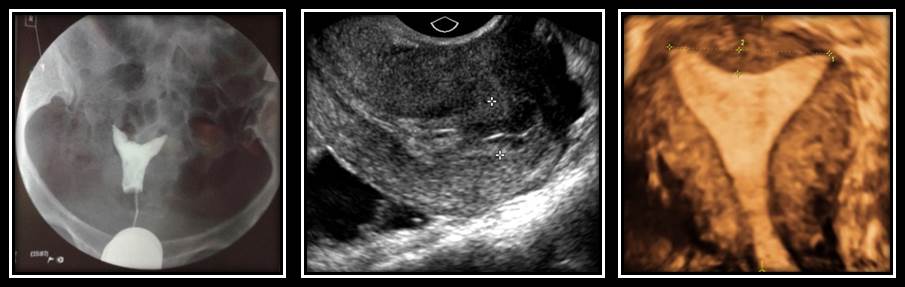

女性患者34岁,孕2产1,继发不孕5年,输卵管碘油造影显示双侧输卵管不通,二维及三维超声提示弓形子宫,其他未见明显异常,而2次行胚胎移植术,但均未获成功,经宫腔镜检查确诊为宫腔多发息肉。